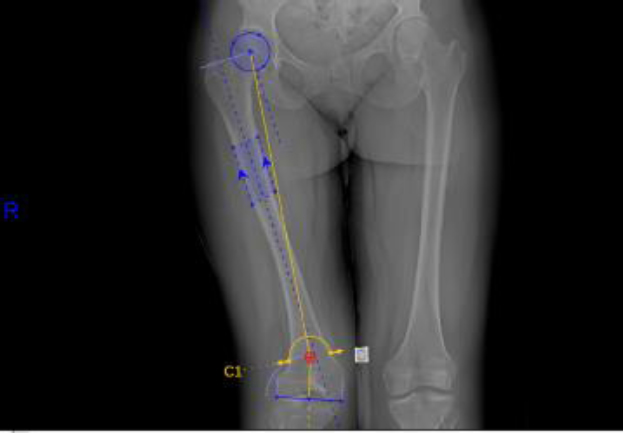

Identifying the proper osteotomy site requires an understanding of the three-dimensional structure of the bone contributing to the deformity, as well as the correction required to restore alignment of the patient’s innate mechanical axis. The pre-operative MAD is measured with bilateral standing hip-to-ankle films with a plumbline connecting the center of the hip to the center of the talus. The MAD is measured from the center of the knee to the mechanical axis line (Fig. 1). Varus deformities have a positive MAD, while valgus deformities have a negative MAD. Joint centers are identified at the hip, knee, and ankle, and the mechanical axes and joint lines are then drawn. This information will determine the joint angles, comparing them to population norm measurements. After analyzing the joint angles, the deformity is identified at either the femur, tibia, or both. The apex of the deformity is identified, which often dictates the location of the planned osteotomy (Fig. 2). Occasionally, the apex of the lower limb deformity is at the knee joint, which requires an alternative location for the osteotomy at the expense of accepting translation after DC. In patients with clinical symptoms and radiographic evidence of unicompartmental osteoarthritis, targeted deformity correction was templated to over-correct for this deformity. Additionally, in 1 patient (patient #18), a postoperative valgus alignment was planned to restore metadiaphyseal alignment for subsequent placement of knee arthroplasty components. As a result, correction of MAD from the preoperative to postoperative state is also reported with targeted/goal correction, as not all patients’ MADs were targeted to 0 mm.

Preoperative analysis of the mechanical axis depicts 40 mm of lateral joint deviation in a patient with right femoral valgus (patient #14). The red dashed line represents the mechanical axis. Lateral distal femoral angle (77°) and medial proximal tibial angle (90.5°) are also shown for reference.